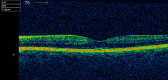

We report a very unusual presentation of primary intraocular lymphoma masquerading as anterior uveitis with atypical symptoms. A 68-year-old man, initially presented with a 4-day history of painless, left blurred vision. Examination revealed 2 or more anterior chamber cells, mutton-fat keratic precipitates and posterior synechiae. Treatment was initiated, the eye settled, and the patient was discharged. He re-presented 7 months later with hypopyon, a hazy cornea, fibrin deposits and a narrowed anterior chamber angle. Over the coming weeks, it became apparent that the temporal iris was thickened, involving the angle, and his intraocular pressure increased despite topical dorzolamide. Following advice from a tertiary centre and referral to a regional ocular oncology centre, a transscleral biopsy was performed and suggested a ciliary body melanoma. Enucleation was advised and performed, with histological examination revealing features consistent with an ocular diffuse large B-cell lymphoma not involving the optic nerve, sclera or cornea. This is the first ever published report of a case of ocular lymphoma masquerading in this way.